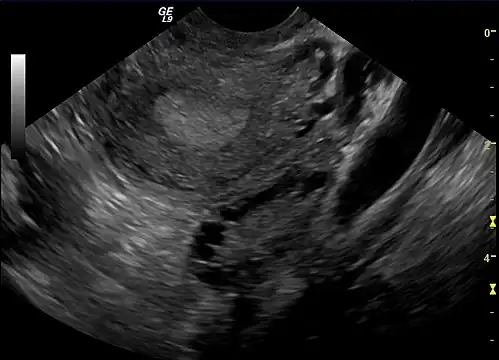

A polycystic ovary

The syndrome acquired its most widely used name due to the common sign on ultrasound examination of multiple (poly) ovarian cysts. These "cysts" are immature ovarian follicles. The follicles have developed from primordial follicles, but this development has stopped ("arrested") at an early stage, due to the disturbed ovarian function. The follicles may be oriented along the ovarian periphery, appearing as a 'string of pearls' on ultrasound examination.[63]

Gynecologic ultrasonography first looks for small ovarian follicles.[75] To count as polycystic ovaries, at least 20 follicles need to be present, smaller than 9 mm. This used to be 12 in older diagnostic criteria.[16] A less clear marker of PCOS is enlarged ovaries.[75] Ovary need to be at least 10 cm3 to count.[16] For sexually active individuals or those that agree, a transvaginal ultrasound approach is preferred. Alternatively, AMH levels can be tested in the blood.[75] Laparoscopic examination may reveal a thickened, smooth, pearl-white outer surface of the ovary. This would usually be an incidental finding if laparoscopy were performed for some other reason, as it would not be routine to examine the ovaries in this way to confirm a diagnosis of PCOS.[78]